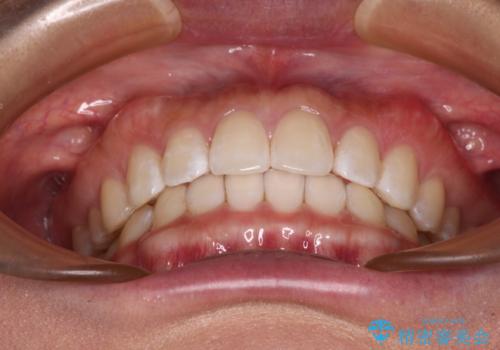

【モニター】前歯のすきっ歯をインビザラインで改善

- 上顎前歯の隙間と口元の突出感を気にして来院された患者様です。

高校生の時に行った矯正治療の後戻りであり、歯列不正は軽度であったので、インビザラインにて治療を行うこととしました。

すきっ歯はあっという間に後戻りを起こすので、可及的に後戻りを防止するために、上下前歯部を舌側からワイヤーで固定しています。

通常は下顎前歯のみに行っていますが、空隙歯列弓では上顎でも行っています。